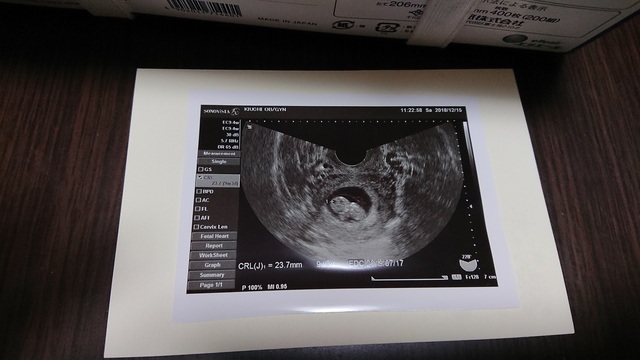

9週2日(9w2d・男の子)|Hubert さん(30歳)

エコー写真撮影時のエピソード:

待ちに待った赤ちゃんの様子がかわいらしくて感動しました。クリスマスの時期だったのでデコレーションをして、サプライズで夫の両親に報告しました。

義理母と義理父はうれしさのあまり大号泣で、産まれてくる前からみんなに歓迎されて愛されているのを実感しました。